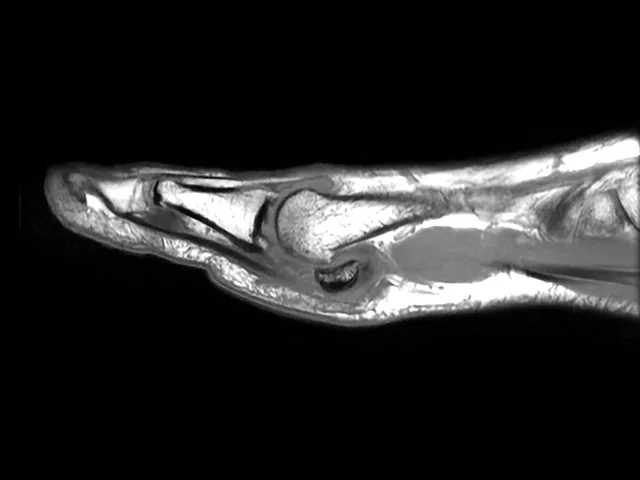

This 3-day Lower Extremity MSK MRI course, led by expert radiologist Dr Phillip Tirman, is designed to elevate your MSK diagnostic skills. Covering MRI techniques for the hip, pelvis, thigh, knee, leg, ankle, and foot, this online radiology course offers a deep dive into essential musculoskeletal imaging with lectures, hands-on case readings, and group discussions.

This Lower Extremity musculoskeletal (MSK) MRI course, taught by highly knowledgeable radiologist Phillip Tirman MD, will include an overview of MRI of the hip and pelvis, thigh, knee, leg, ankle, and foot with a daily presentation, individual case readings, and group-based case read-outs.

• Talks on general MSK Imaging of injuries of the lower extremity.